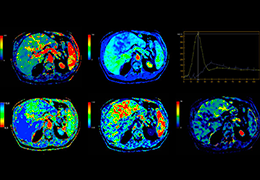

ANYTHINK 经导管主动脉瓣膜置换术分析系统